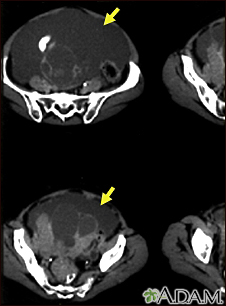

Ascites with ovarian cancer - CT scanBackAscites with ovarian cancer - CT scanThis CT scan of the lower abdomen shows a massive amount of free abdominal fluid (ascites) in a patient with ovarian cancer. E-mail FormEmail ResultsName:Email address:Recipients Name:Recipients address:Message: